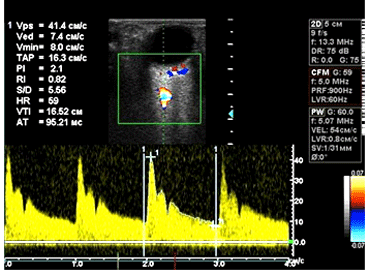

Оценка показателей кровотока в ГА, ЦАС и ЗКЦА производилась при помощи ультразвуковой допплерографии (УЗДГ) на многоцелевой диагностической системе Vivid 3 (General Electric, Израиль) с исполь-зованием линейного датчика с частотой 13,3 МГц в импульсном режиме. Гемодинамические характеристики определяли в ГА на отрезке до образования ее дуги над зрительным нервом (на расстоянии 10,1 – 14,9 мм от заднего полюса глазного яблока), в ЦАС – 1,5 – 3,0 мм от заднего полюса в пределах диска зрительного нерва, в ЗКЦА – 0,7 – 0,33 мм от заднего полюса глазного яблока в непосредственной близости от зрительного нерва. Количественная оценка глазного кровотока включала следую-щие амплитудные параметры и индексы допплерограммы:

С целью изучения характера кровотока в сосудах глаза и орбиты мы проанализировали параметры ультразвуковой допплерографии в ГА, ЦАС и ЗКЦА.

Для оценки полученных результатов пациенты были разделены на группы в зависимости от длины переднезадней оси глаза (ПЗО). В I группу вошли пациенты с ПЗО – 23,37 ± 0,52мм, преимущественно с эмметропической рефракцией и миопией слабой степени. Во II группу были включены пациенты с миопией средней и высокой степени и средней величиной ПЗО – 26,41 ± 0,67мм. Различий в показателях кровотока в ГА выявлено не было. Показатели гемодинамики в ЦАС представлены на рис. 2.

Сравнение производили с группой контроля и с парными «здоровыми» глазами. Так, анализ результатов кровотока в ГА выявил достоверное снижение только V max у пациентов первой группы относительно контроля, при нормальных значениях V min и V med. RI и PI были снижены. При осложненном течении и на парных глазах уровень кровотока в ГА не отличался от нормы (рис. 3).

Рис. 3. Спектр кровотока в ГА при осложненном характере течения ПВХРД